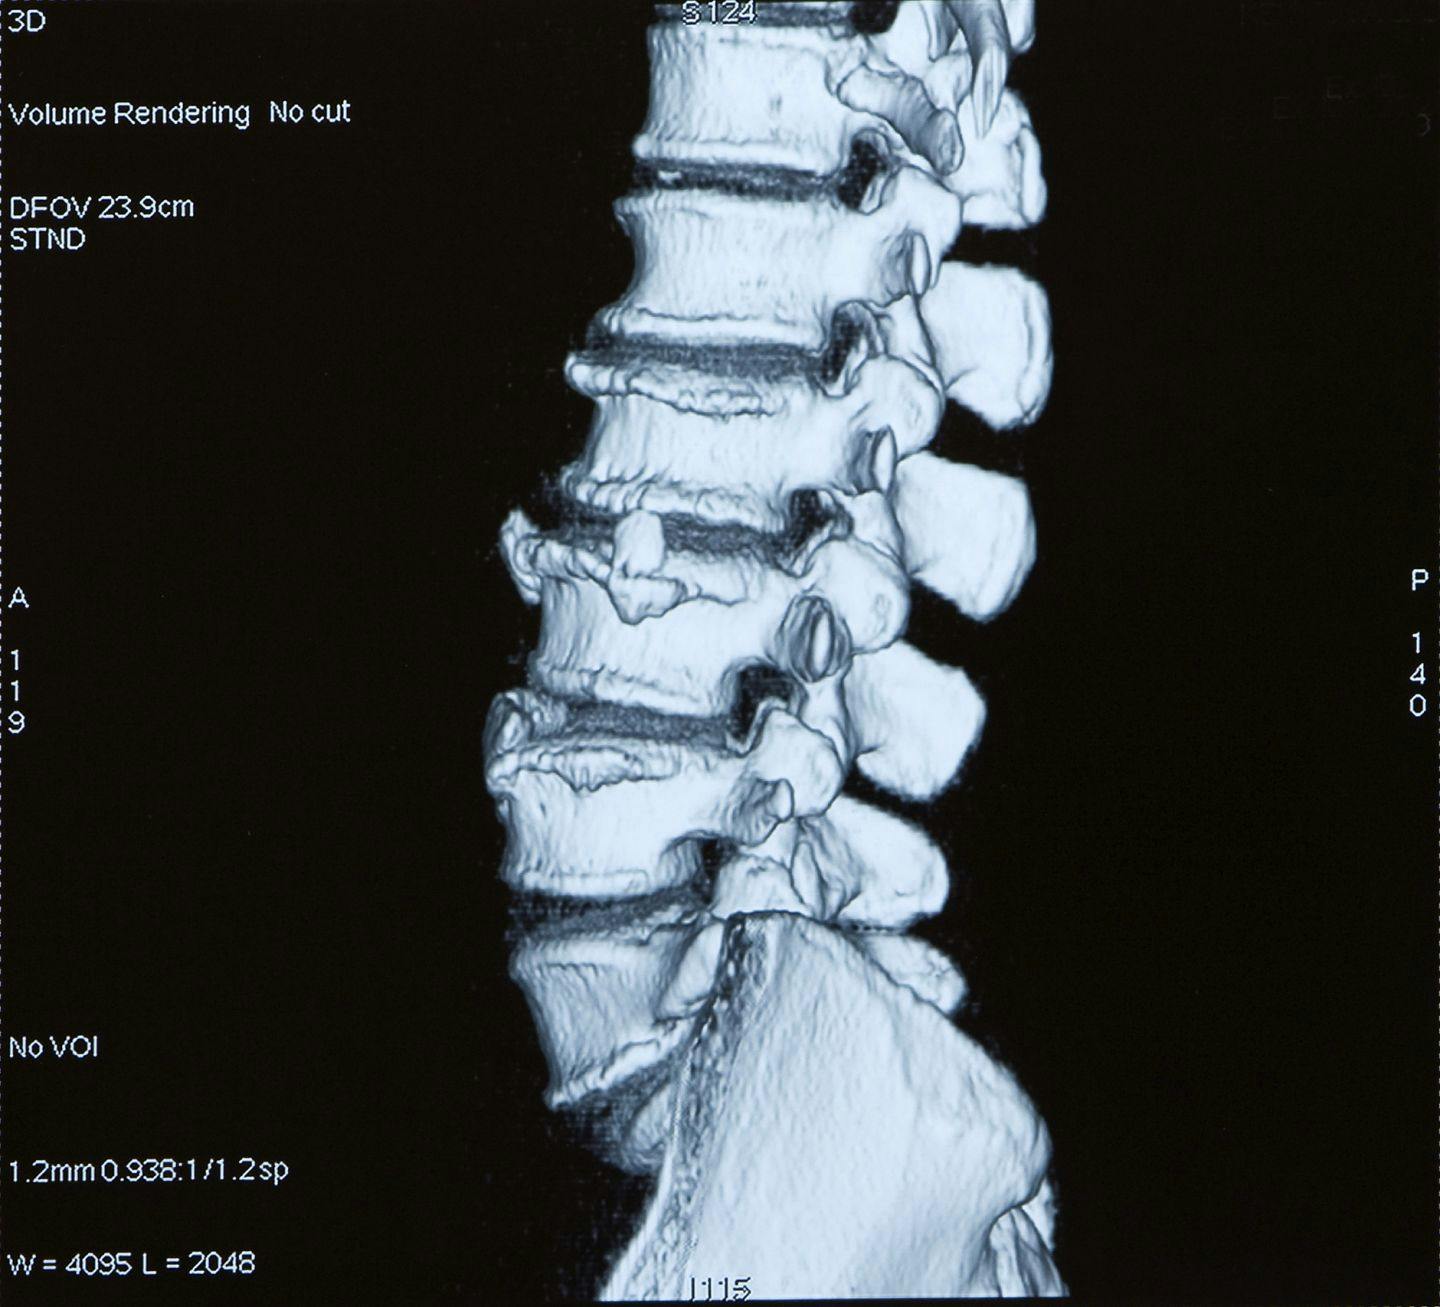

- Slipped/Herniated Disc

- Arthritis

- Spondylosis

- Spondylolysis

- Spondylolisthesis

- Facet Arthropathy

- Degenerative Disc Disease